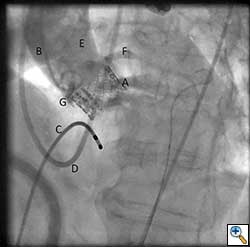

After valve implantation, it is critical to confirm valve competence, visualize coronary flow, and check for aortic injury by performing echocardiography and completion angiography (Figure 3). In the stabilized patient, the large femoral sheath is removed while maintaining wire access, ensuring no damage to the iliac artery. Once flow is confirmed in the proximal and distal femoral artery, the guidewire can be removed. The artery is clamped on either side and the arteriotomy is closed primarily with interrupted 5-0 or 6-0 prolene. The incision site is closed in standard fashion with absorbable suture in layers. The femoral arterial and venous sheaths in the contralateral groin may be left in place and then removed when the activated clotting time reverses to normal. Patient is taken back to the cardiothoracic intensive care unit for postoperative recovery.